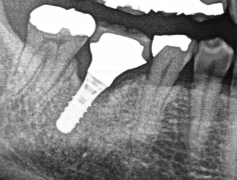

└4MTA

今回はMTAセメントの症例をご紹介します?

☆クリーニングで虫歯が見つかり処置

☆左上4

?MTAセメント?

・マイクロ下で処置、動画も撮影

・処置時間1時間

・¥55,000

【担当医】北野 展久